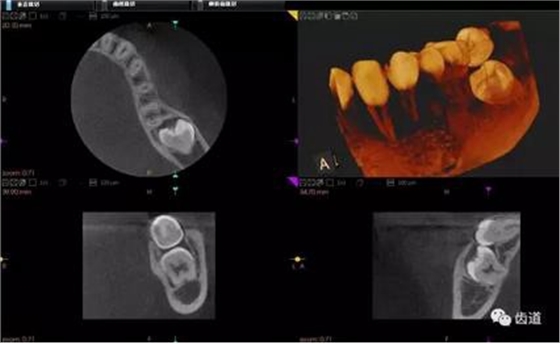

1、下頜骨種植牙前測量準(zhǔn)備影像

2、上頜骨種植牙前準(zhǔn)備影像

3、下頜骨種植牙術(shù)后